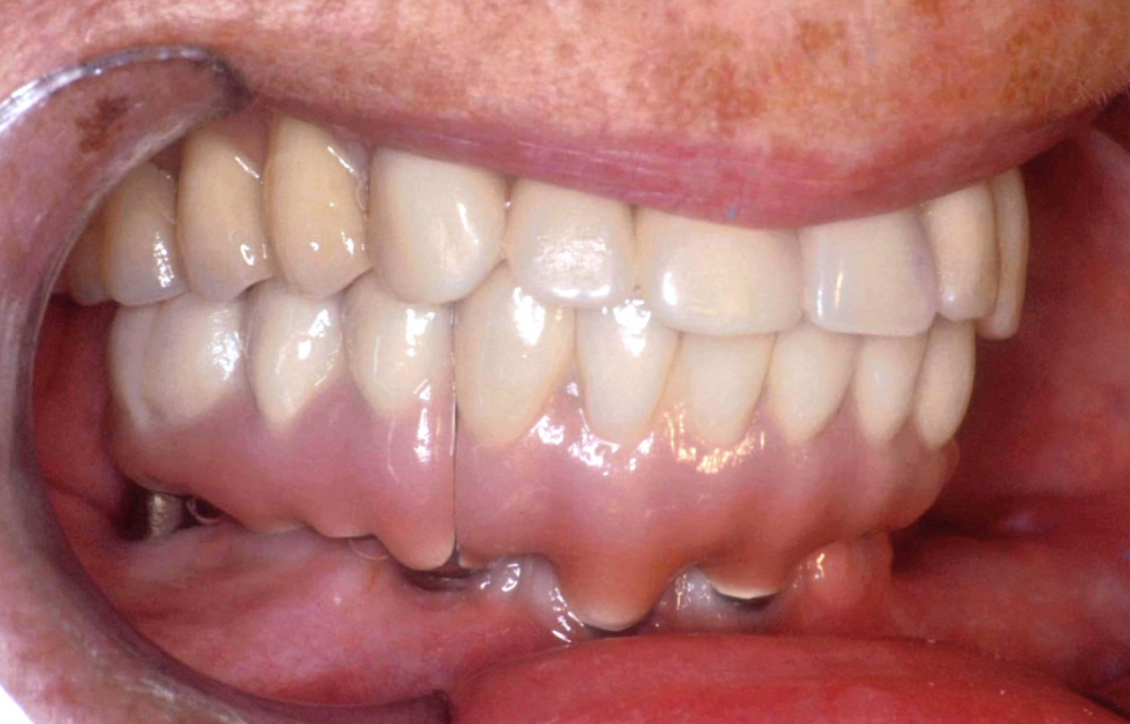

(3.) Prosthesis without access to the intaglio interface.

Figure 3

(4.) Intagilo inflammation of the soft tissue following removal of the prosthesis.

Figure 4

(5.) Prosthesis intaglio surface.

Figure 5

(6.) Flange makes intaglio interface inaccessible.

Figure 6